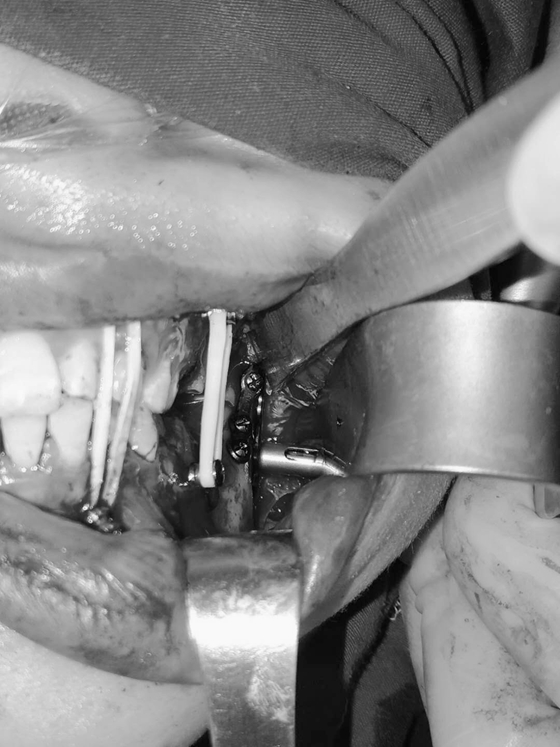

在为患者消肿抗炎治疗后,由伍栋副主任医师主刀,康霄主治医师、向峰医师和刘明军医师共同协助,4月10日为患者实施了下颌骨切开复位内固定术+颌间牵引固定术。术中,口腔科医生通过穿颊器在面部与下颌骨之间打通了一条“隧道”,手中的器械就能通过这个“隧道”直达复位固定处发挥用处。手术完成,患者面部仅留下不到1公分的小创口,既达到了患者的美观需求,还保证患者能得到了很好的治疗。